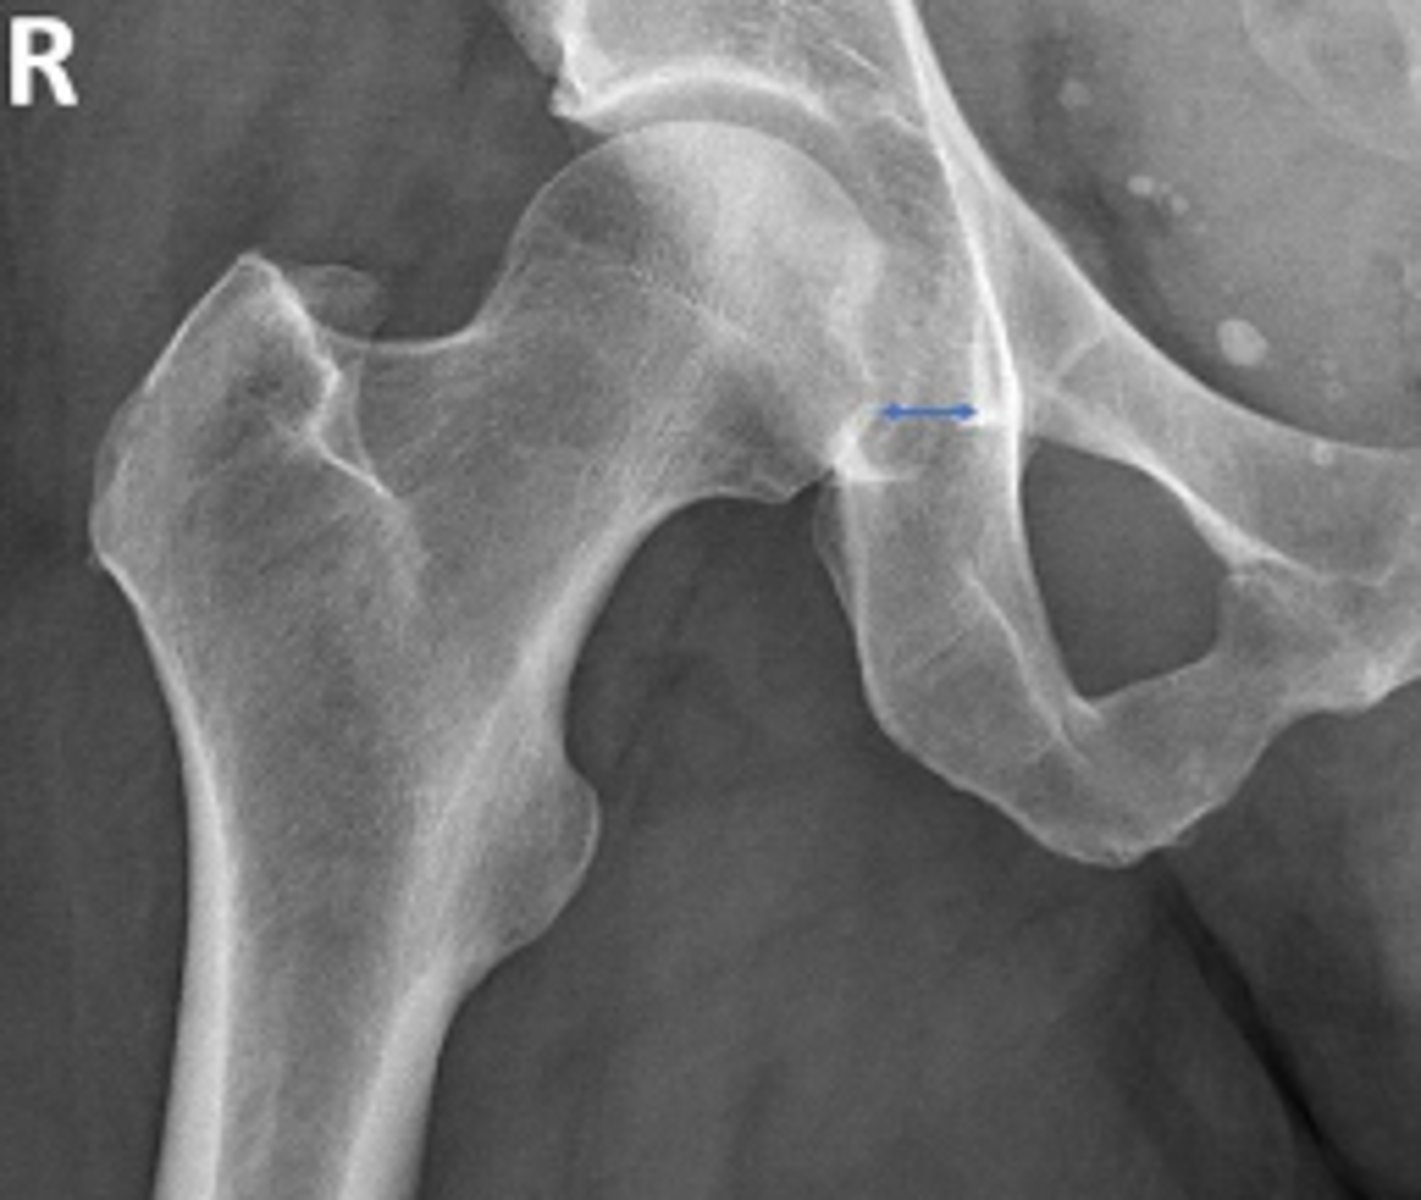

Right AP hip

What is the name of the radiographic view?

Posterior rim of the right acetabulum

What are the arrows pointing to?

Anterior rim of the right acetabulum

Lesser trochanter of the right femur

Greater trochanter of the right femur

Intertrochanteric line of the right femur

Right ischial tuberosity

Right iliopectineal line

What is the name of the assessment?

Right ilioischial line